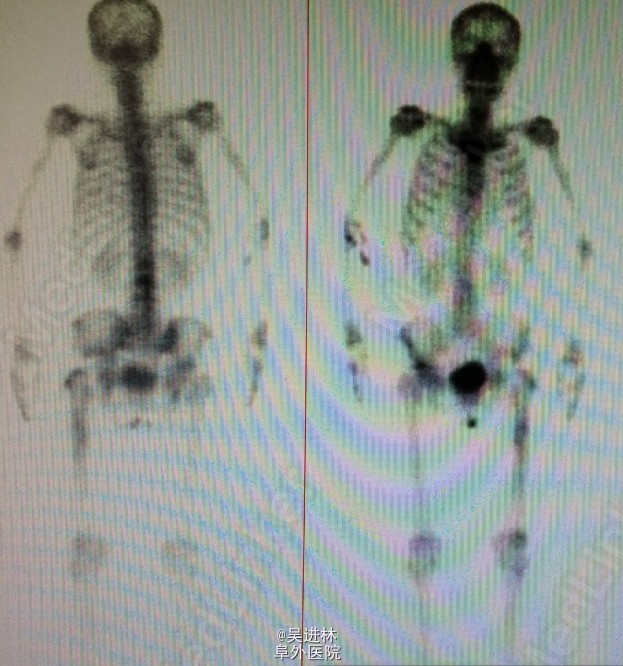

患者老年女性,63岁,主因:左侧全髋关节置换术后一年,疼痛3月入院。患者一年前因股骨头坏死行手术,三月前无明显诱因出现左髋部疼痛,以左大腿明显,呈钝痛,活动后疼痛。 患者查体局部无红肿热,ESR,CRP正常;骨扫描左大腿有浓集灶。今日讨论,有的主任认为是低度感染,有的认为是假体不适造成(如图,该假体旋转中心不在同一水平,型号大),更有主任说德国人遇到这种情况全部当感染来翻修。你怎么看呢?目前怎么处理?